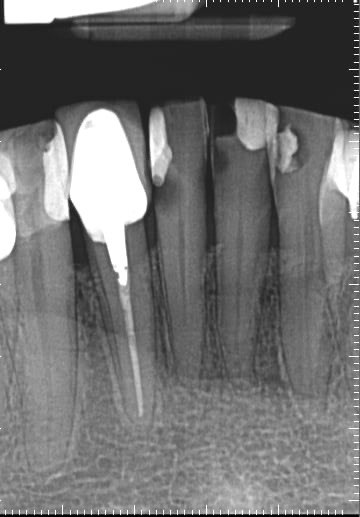

Question 1: What materials cannot be seen in the print of the X ray?

Question2: Which surface shows overhang?

Question 3: Which option is not evident on the print of the X ray?

Question 4: Which options cannot be seen in the print of the X ray?

Question 5: What options cannot be selected for tooth # 4.6?

Question 6: What options cannot be seen in the print of the X ray?

Question 7: What option cannot be identified on the print of the X ray?

Question 8: What condition can be seen in the X ray?

Question 9: Which option cannot be seen in the lower jaw?

Question 10: Which option can be selected for the following X ray?

Question 11: Which materials cannot be seen in the print of the X ray?

Question 12: What option cannot be selected for the following X ray?

Question 13: What option cannot be selected for the following X ray?

Question 14: Which surface shows overhang restoration?

Question 15: Which surface shows overhang in the restoration?

Question 16: Which surface shows overhang?

Question 17: Which surface shows overhang?

Question 18: Which surface shows overhang?

Question 19: Which option can be chosen for the tooth # 3.6?

Question 20: which tooth shows defective resotration?

Question 21: What option is can be selected for distal tooth # 4.6?

Question 22: Which surface shows defective restoration?

Question 23: Which surface shows overhang?

Question 24: Which surface shows defective restoration?

Question 25: Which surface shows open margin?